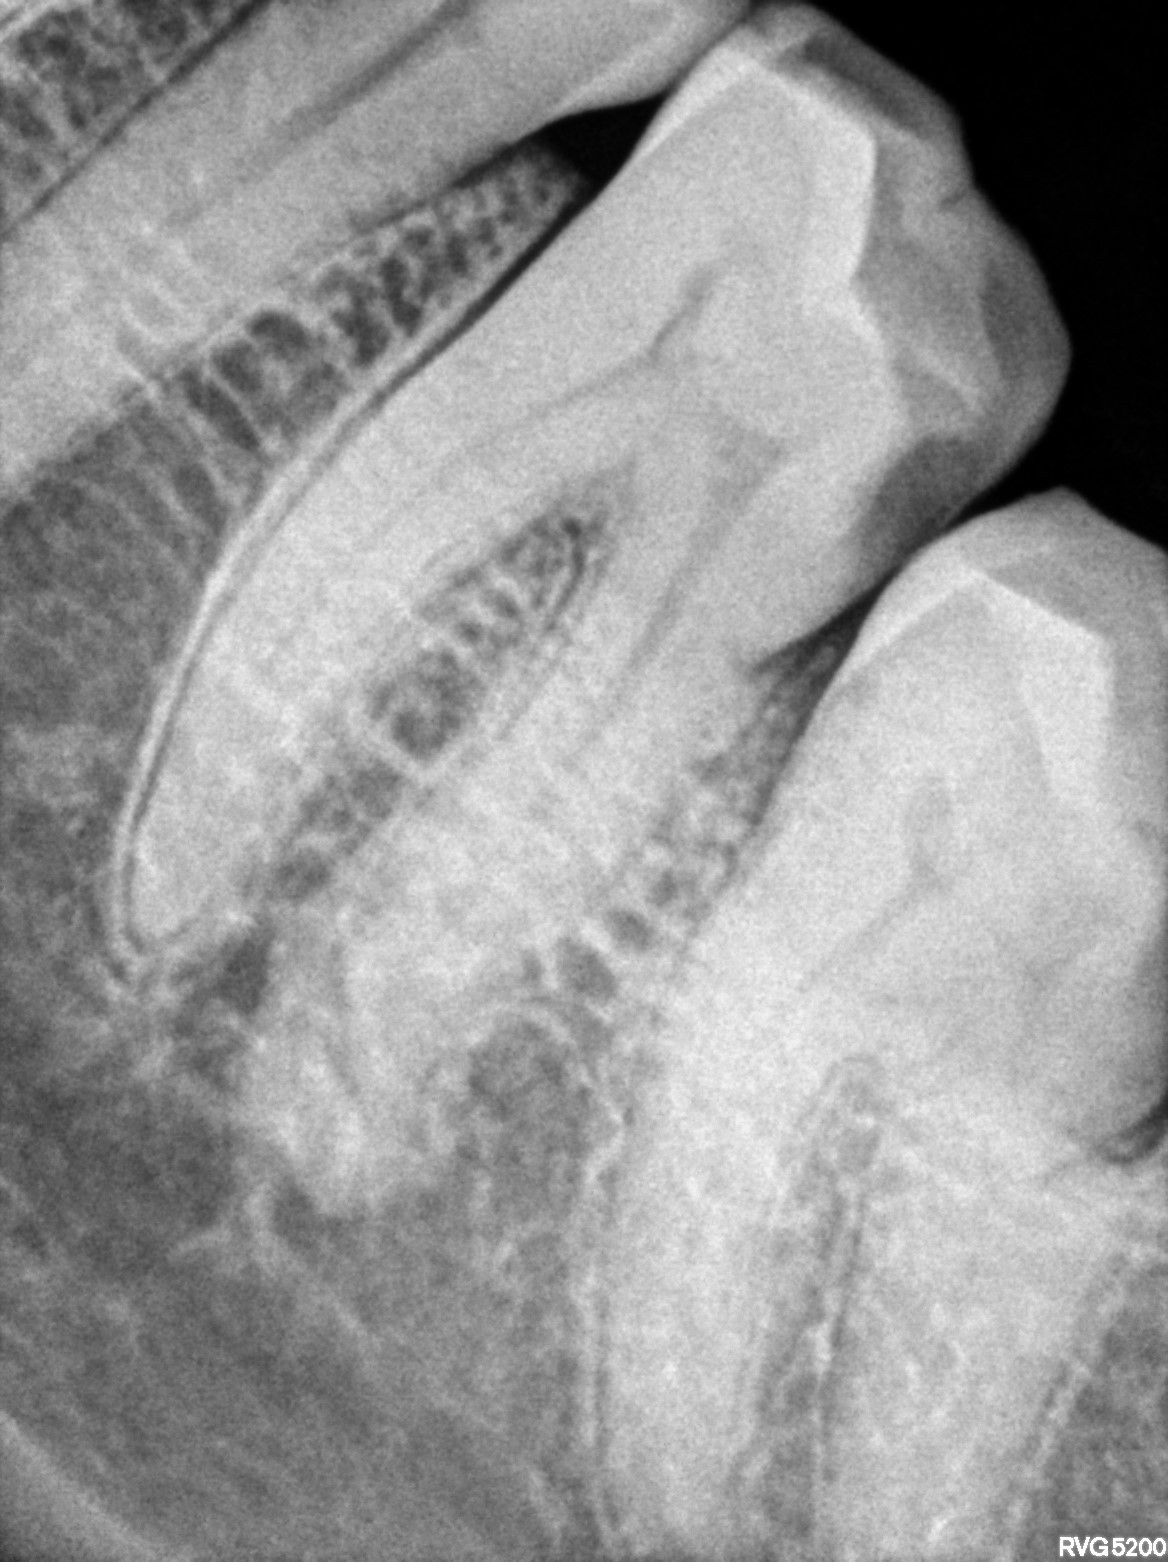

Dental Radiographs FHIR: DocumentReference · LOINC 24641-7

xray_1747409705_1.jpg

24641-7